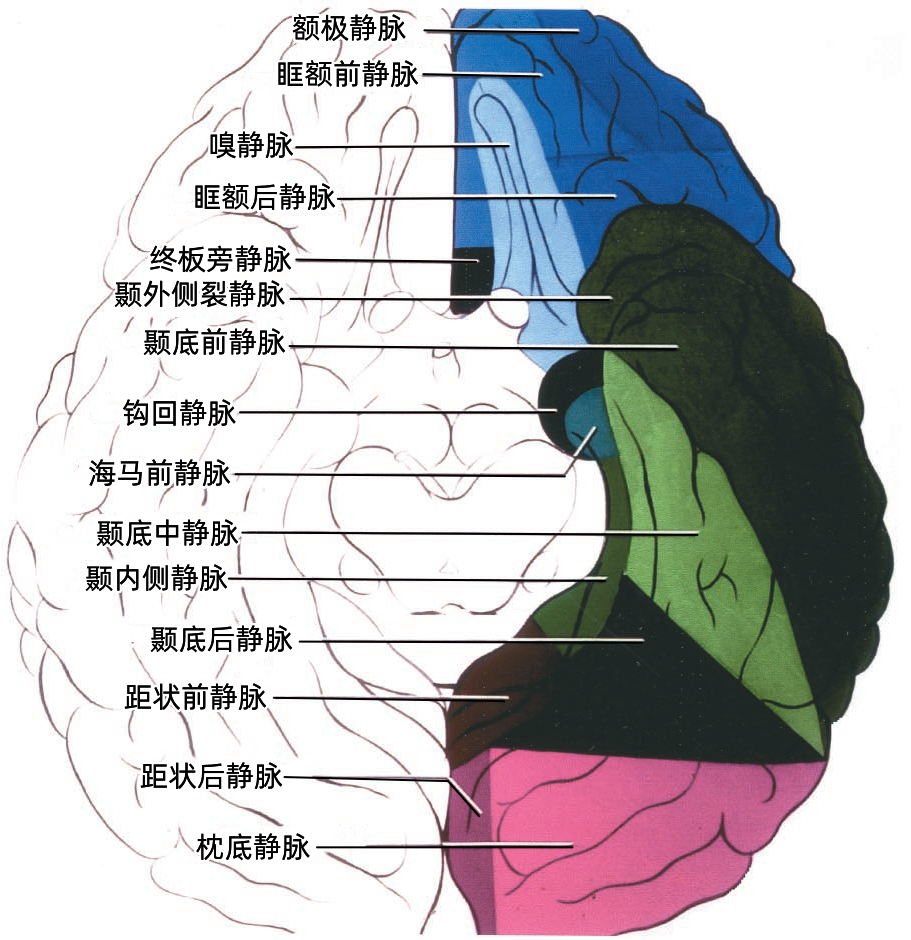

额叶底面(蓝色)由额极静脉、眶额前静脉、眶额后静脉,嗅静脉和终板旁静脉引流。 颞叶底面(绿色)由颞底前静脉、颞底中静脉、颞底后静脉、海马前静脉、钩回静脉、颞内侧静脉、颞外侧裂静脉。

额叶底面的静脉按引流方向由两种蓝色标出:浅蓝色为前组静脉,进入上矢状窦。深蓝色为后组静脉,进入基底静脉前端。额底静脉的前组是眶额前静脉;后组包括眶额后静脉和嗅静脉。 颞叶底面的静脉按引流方向由两种绿色标出:深绿色标注的静脉向外侧走行汇入小脑幕窦。浅绿色标注的静脉向内侧走行汇入基底静脉。向外侧走行的颞底静脉包括颞底前静脉、颞底中静脉、颞底后静脉;向内侧走行的颞底静脉包括海马前静脉、钩回静脉、颞内侧静脉。 枕叶底面只有一支即枕下静脉,由紫色标出,汇入小脑幕窦。大脑内静脉汇入Galen静脉。